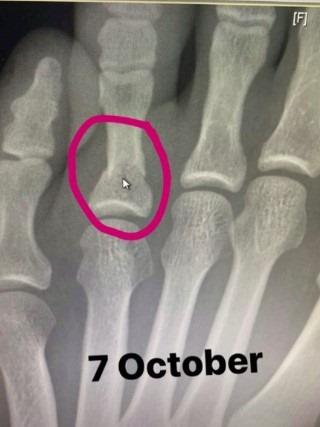

Prvi čovek ove organizacije Dejna Vajt nakon borbe je izjavio da je Habib imao prelom stopala, a Degistanac je sada to i potvrdio.

On je na Instagramu objavio rengenski snimak preloma i fotografiju otečenog stopala. Verovali ili ne, prelom je doživeo svega 16 dana pred borbu za titulu. Zbog toga je njegova pobeda nad sjajnim Gejdžijem još fascinantnija.

Habib nije želeo da iko pred borbu sazna da ima problem, nije se žalio, a u oktagonu niko nije mogao da primeti da mu nešto fali. Istrpeo je bol i na impresivan način odbranio titulu.